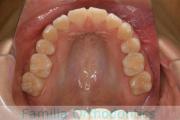

上の前歯の並びが気になるのできれいにしたい、ということで来院されました。マウスピース型矯正装置のひとつ、インビザライン/InvisalignR(薬機法および医薬品副作用被害救済制度の対象外)を用いて治療しました。

非抜歯で2年弱、20回程度の通院で治療が完了しました。

マウスピース矯正は、患者さんの協力に治療結果が左右されるところはリスクと言えるかもしれません。